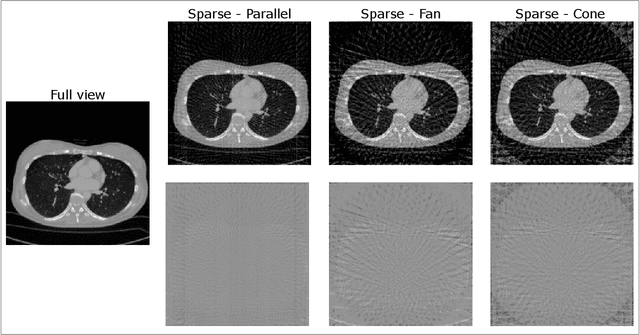

Abstract:This study aims to investigate the effect of various beam geometries and dimensions of input data on the sparse-sampling streak artifact correction task with U-Nets for clinical CT scans as a means of incorporating the volumetric context into artifact reduction tasks to improve model performance. A total of 22 subjects were retrospectively selected (01.2016-12.2018) from the Technical University of Munich's research hospital, TUM Klinikum rechts der Isar. Sparsely-sampled CT volumes were simulated with the Astra toolbox for parallel, fan, and cone beam geometries. 2048 views were taken as full-view scans. 2D and 3D U-Nets were trained and validated on 14, and tested on 8 subjects, respectively. For the dimensionality study, in addition to the 512x512 2D CT images, the CT scans were further pre-processed to generate a so-called '2.5D', and 3D data: Each CT volume was divided into 64x64x64 voxel blocks. The 3D data refers to individual 64-voxel blocks. An axial, coronal, and sagittal cut through the center of each block resulted in three 64x64 2D patches that were rearranged as a single 64x64x3 image, proposed as 2.5D data. Model performance was assessed with the mean squared error (MSE) and structural similarity index measure (SSIM). For all geometries, the 2D U-Net trained on axial 2D slices results in the best MSE and SSIM values, outperforming the 2.5D and 3D input data dimensions.